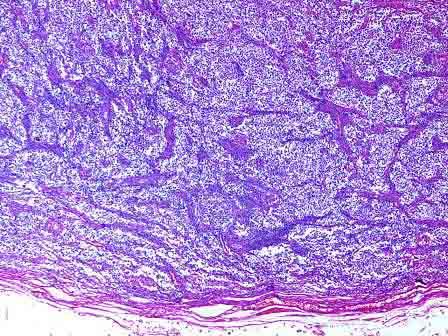

问题 男性,57岁,因左侧睾丸进行性肿大行睾丸切除。大体见肿瘤切面呈鱼肉状,境界清楚,米黄色,质均,略呈分叶状(如图)。镜下见形态单一的细胞群被薄层纤维血管带分成小叶状,肿瘤细胞体积大,大小一致,胞浆丰富透明,细胞膜清楚(如图),免疫组化染色PLAP(+)。应诊断为 ( )

选项 A.睾丸精原细胞瘤 B.睾丸胚胎性癌 C.睾丸未分化畸胎瘤 D.睾丸间质细胞瘤 E.睾丸精原母细胞瘤

答案 A